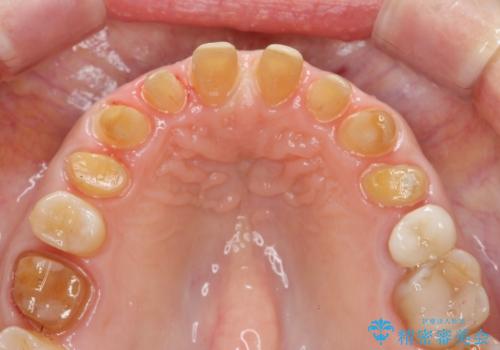

- 十数年前に行った、前歯のラミネートベニアの継ぎ目が見えるようになってきて見た目が気になる。

この際もう一度ラミネートでやり替えるのではなく、強度にも優れるクラウンにしたいと希望され来院されました。

ラミネートを丁寧に除去したのち、ジルコニアクラウンを作製し審美性の回復・向上を計画します。